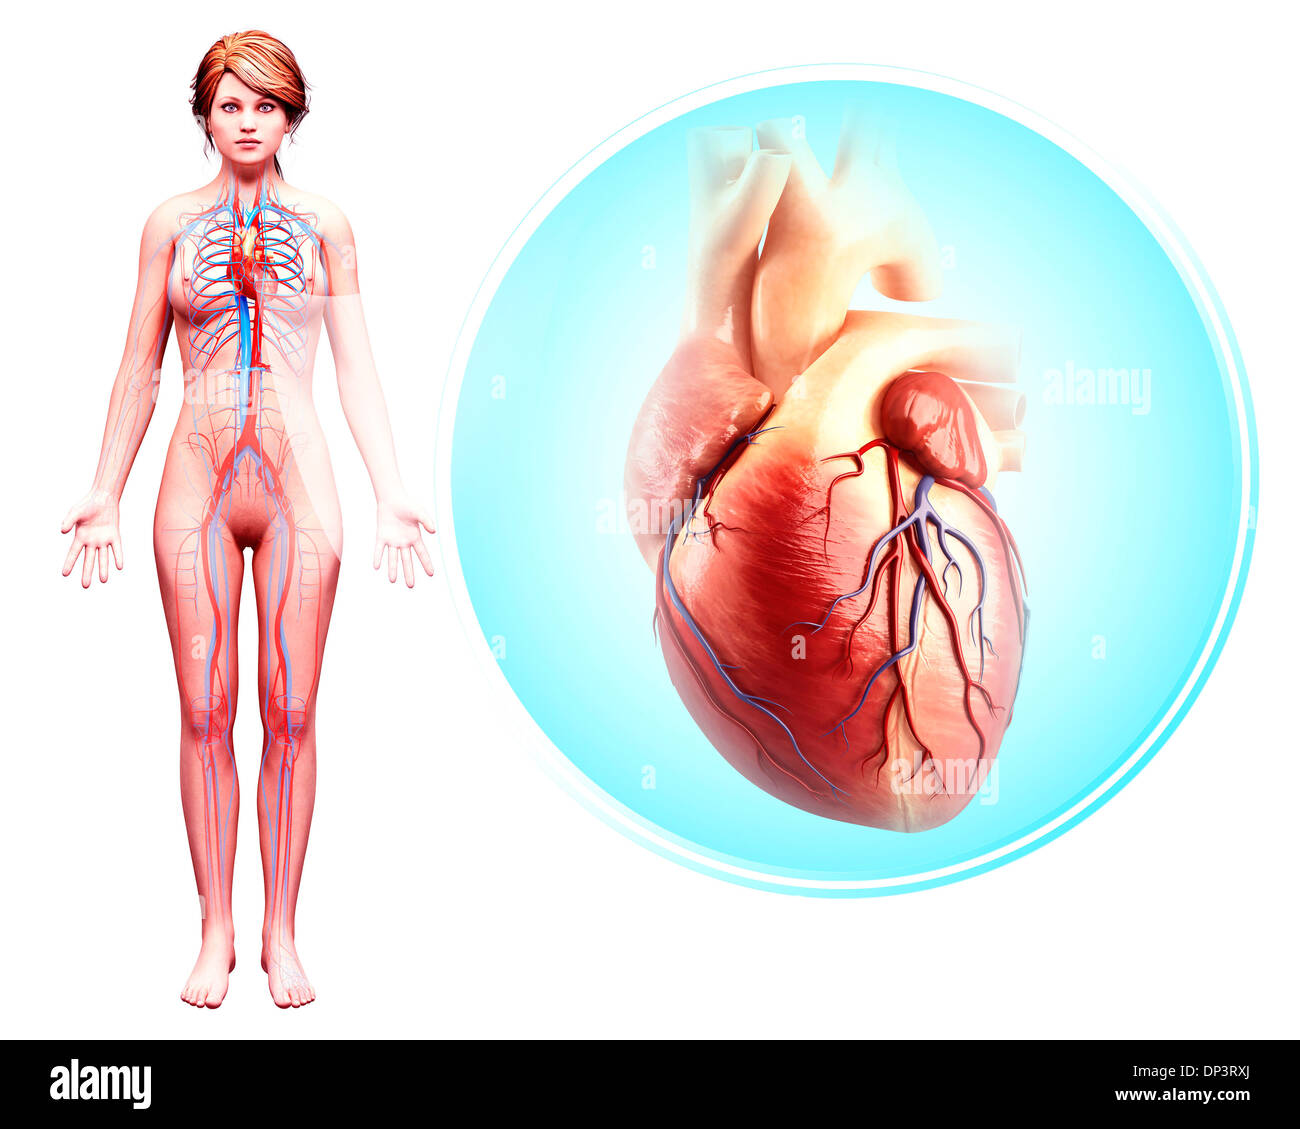

Système cardiovasculaire, artwork Banque D'Imageshttps://www.alamyimages.fr/image-license-details/?v=1https://www.alamyimages.fr/photo-image-systeme-cardiovasculaire-artwork-55415491.html

Système cardiovasculaire, artwork Banque D'Imageshttps://www.alamyimages.fr/image-license-details/?v=1https://www.alamyimages.fr/photo-image-systeme-cardiovasculaire-artwork-55415491.htmlRFD64B0K–Système cardiovasculaire, artwork